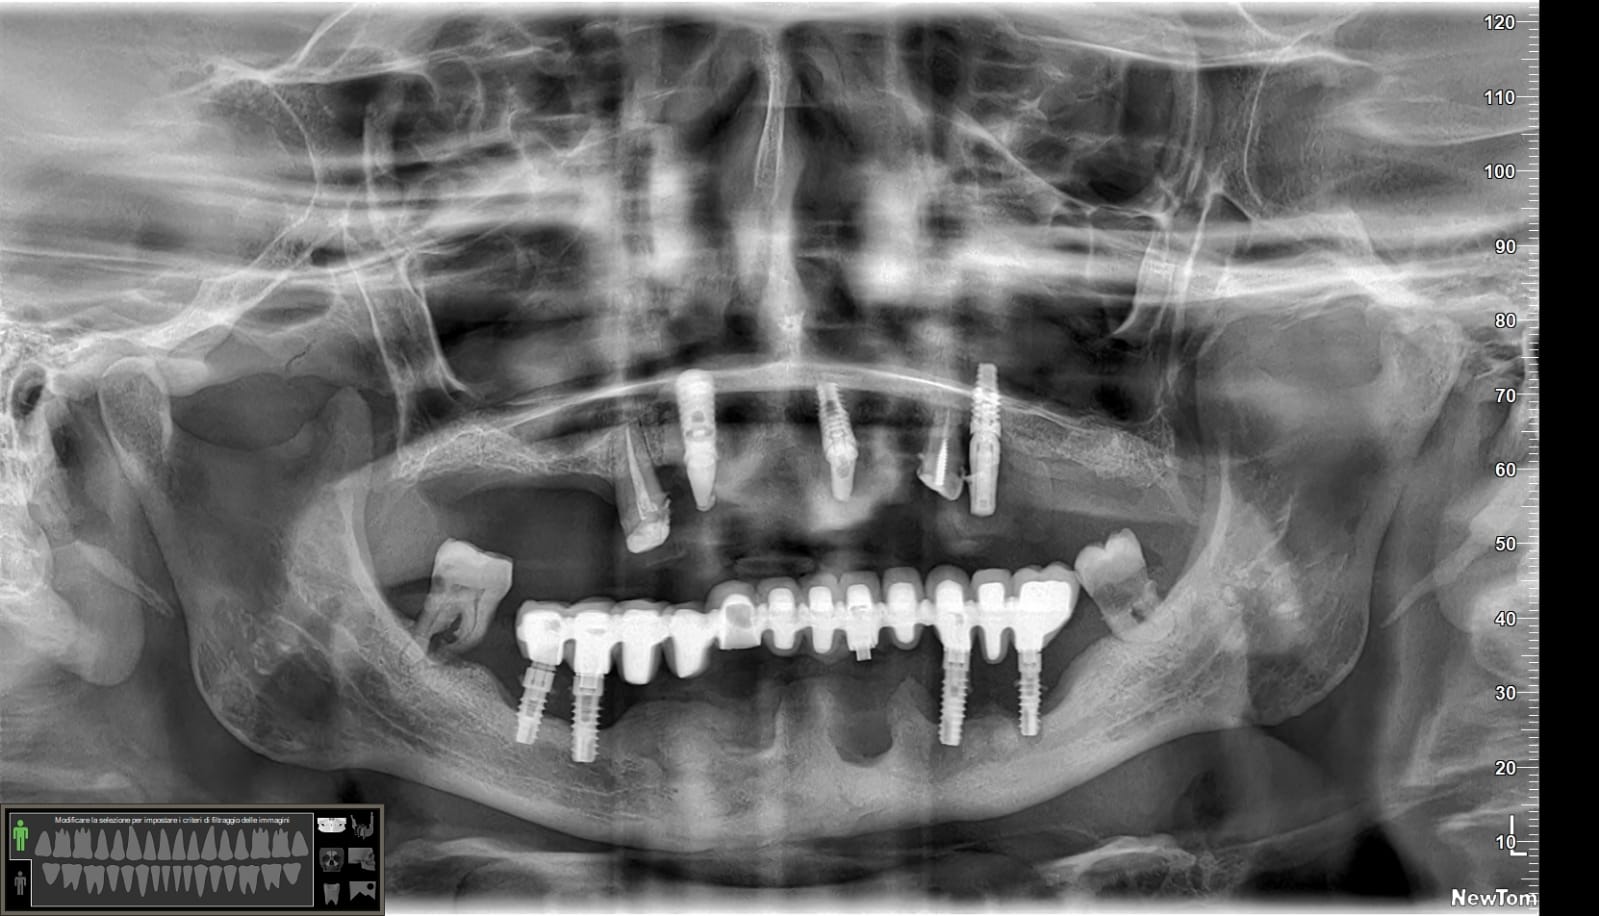

Vedo ancora molti colleghi che vanno in crisi per casi come questo.😒

Effettivamente ci sono impianti vecchi da rimuovere e l’osso è scarso.

Nel caso di oggi vedremo il posizionamento di un impianto transinusale in questo paziente:

Ah… questa è la panoramica finale, inferiormente non ho trovato il modo per mettere 4 impianti ma solo tre… vedremo se aggiungerne uno. E non farti ingannare dall’immagine: il mentoniero di destra non è quello che sembra più distale ma quello meno visibile più mesiale.😎